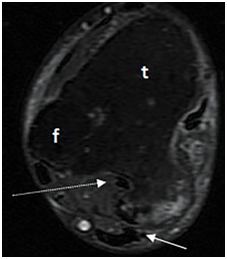

MRI also revealed subtalar degeneration as narrowing of the joint space, subchondral trabecular edema, and cystic changes on sagittal images (Figure 3). Flexor hallucis longus tendon was displaced and entrapped by the exophytic tumor (Figure 4).

Figure 4 Axial proton density weighted fat saturated (TR/TE,2250/33) MR image showes tibiofibular fusion via an osteochondroma, causing flexor hallucis longus tendon entrapment (arrow) and mildly compression of achilles tendon (dotted arrow). T, tibia, f, fibula.